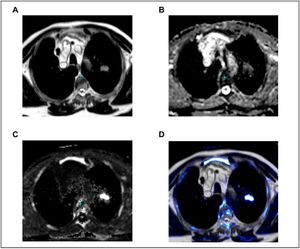

Quantification of Diaphragm Mechanics in Pompe Disease using Dynamic 3D MRI

Publication: PLoS One. 2016 Jul 8;11(7):e0158912. PMID: 27391236 | PDF Authors: Mogalle K, Perez-Rovira A, Ciet P, Wens SC, van Doorn PA, Tiddens HA, van der Ploeg AT, de Bruijne M. Institution: Biomedical Imaging Group Rotterdam, Departments of Medical Informatics & Radiology, Erasmus MC, Rotterdam, the Netherlands. Background/Purpose: Diaphragm weakness is the main reason for respiratory dysfunction in patients with Pompe disease, a progressive metabolic myopathy affecting respiratory and limb-girdle muscles. Since respiratory failure is the major cause of death among adult patients, early identification of respiratory muscle involvement is necessary to initiate treatment in time and possibly prevent irreversible damage. In this paper we investigate the suitability of dynamic MR imaging in combination with state-of-the-art image analysis methods to assess respiratory muscle weakness. Methods: The proposed methodology relies on image registration and lung surface extraction to quantify lung kinematics during breathing. This allows for the extraction of geometry and motion features of the lung that characterize the independent contribution of the diaphragm and the thoracic muscles to the respiratory cycle. Results: Results in 16 3D+t MRI scans (10 Pompe patients and 6 controls) of a slow expiratory maneuver show that kinematic analysis from dynamic 3D images reveals important additional information about diaphragm mechanics and respiratory muscle involvement when compared to conventional pulmonary function tests. Pompe patients with severely reduced pulmonary function showed severe diaphragm weakness presented by minimal motion of the diaphragm. In patients with moderately reduced pulmonary function, cranial displacement of posterior diaphragm parts was reduced and the diaphragm dome was oriented more horizontally at full inspiration compared to healthy controls. Conclusion: Dynamic 3D MRI provides data for analyzing the contribution of both diaphragm and thoracic muscles independently. The proposed image analysis method has the potential to detect less severe diaphragm weakness and could thus be used to determine the optimal start of treatment in adult patients with Pompe disease in prospect of increased treatment response. Funding:

Mesh representation of 3D lung segmentation. A trained medical observer manually segmented right and left lung in both static scans (inspiration and expiration) of each subject by tracing the lung surface in every second axial slice using 3D Slicer. |